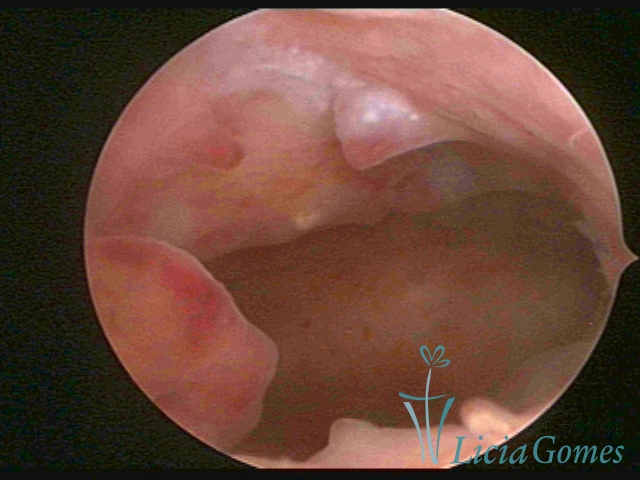

Complex Hyperplasia has a pseudopolypoid aspect which resembles cerebroid tissue or with decidual reaction. The superficial vascularization is more evident, presenting vessels in the shape of corkscrew or spiral.

Atypical hyperplasia and histeroscopical aspect are similar to complex hypertrophy, also presenting vascularization with atypias. With the increase of the thickness of the superficial vessels, tissues in necrosis may also be found.